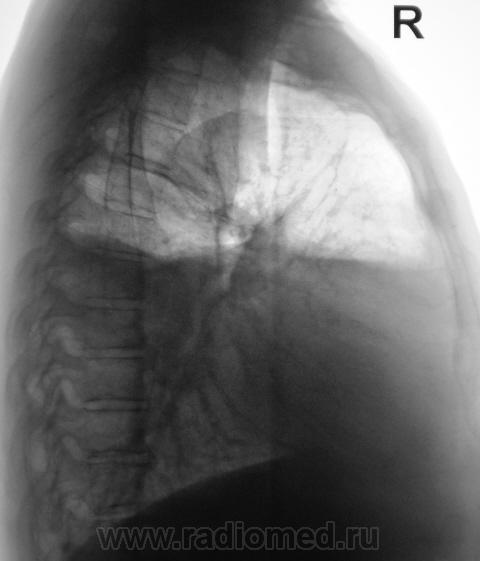

Признаков пневмоторакса по прямой R-грамме не нахожу( в наружном отделе среднего поля справа, явно не воздух т.к.тень значительно плотнее лёгочной ткани), по боковой проекции действительно видна жидкость с горизонтальным уровнем-может быть этот уровень имеет отношение к средостению? Случай непростой, нужна клиника и анамнез.

Уровень сохраняется горизонтальный за счет осумкования так как не растекается на томограммах.Пневмоторакс сомнителен. А вот причина плеврита ?

- вызывает сомнение полоса просветления в мягких тканях гр. клетки справа, там где стрелка виднеется;

- разница в плотности мягких тканей надключичной области;

- переломы ребер справа - мозолей не видно. С ребрами слева всё ясно.

Свернувшаяся гематома в плевральной полости не будет гулять(растекаться) - это что-то вроде холодца, имеется ввиду по плотности.То, что снимали стоя - говорит о более-менее стабильном состоянии бедолаги.

О пневмотораксе говорит светлая полоса по краю легочного поля справа - там и не прослеживается легочной рисунок.(Во всяком случае на моём мониторе.